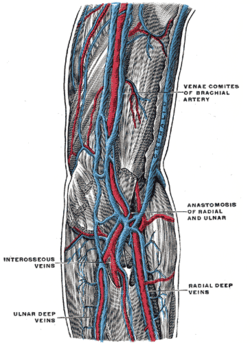

Blood supply

The arteries supplying the joint are derived from an extensive circulatory anastomosis between the brachial artery and its terminal branches. The superior and inferior ulnar collateral branches of the brachial artery and the radial and middle collateral branches of the profunda brachii artery descend from above to reconnect on the joint capsule, where they also connect with the anterior and posterior ulnar recurrent branches of the ulnar artery; the radial recurrent branch of the radial artery; and the interosseous recurrent branch of the common interosseous artery.[12]

The blood is brought back by vessels from the radial, ulnar, and brachial veins. There are two sets of lymphatic nodes at the elbow, normally located above the medial epicondyle — the deep and superficial cubital nodes (also called epitrochlear nodes). The lymphatic drainage at the elbow is through the deep nodes at the bifurcation of the brachial artery, the superficial nodes drain the forearm and the ulnar side of the hand. The efferent lymph vessels from the elbow proceed to the lateral group of axillary lymph nodes. [12] [13]